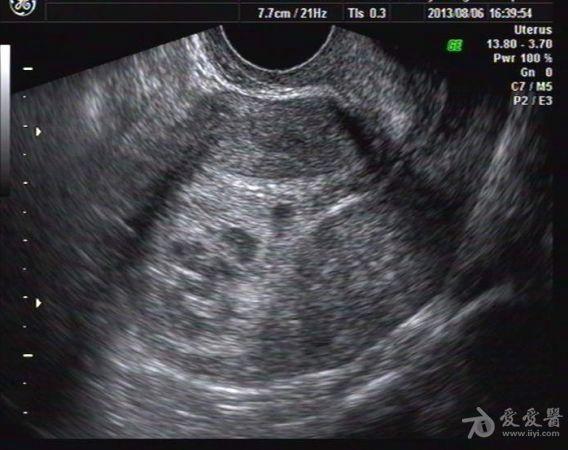

停经47天血HCG大于1万,未稀释 我院B超:子宫大小57x55x61mm,宫内探及一大小约34x27x43mm强回声团块,内回声紊乱,夹杂多个不规则暗区,暗区内未见胚芽及胎心搏动。

该病人子宫增大不明显,无腹痛流血。

手术病检证实:葡萄胎